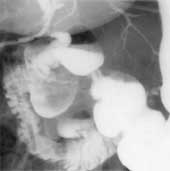

2. Больная П., 52 лет поступила в хирургию с жалобами на периодически возникающую

желтуху. УЗИ исключило наличие у больной конкрементов. Была проведена холангиография

по дренажной трубке, находившейся в желчных протоках, с одновременным контрастированием

желудка и двенадцатиперстной кишки барием. Причиной желтухи оказался огромных

размеров дивертикул, который при наполнении оттеснял общий желчный проток, что

периодически нарушало отток желчи, вызывая механическую желтуху (Рис. 2).

Рис. 2. Большой дивертикул сдавливает и смещает общий желчный

проток.